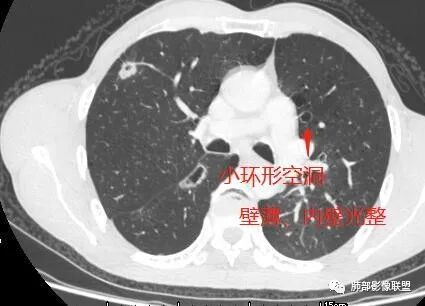

(2)小环形空洞 ,呈圆形 ,壁薄 (2 ~ 4 mm)而均匀 ,直径≤15 mm, 内壁光整;

其中囊样空洞和小环形空洞属于薄壁空洞,泡样空洞和不规则空洞属于厚壁空洞,其中腺癌空洞型肺转移瘤主要表现为小环形空洞,以下3个病例均表现为小环形空洞的转移瘤: